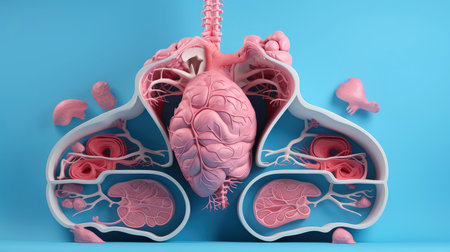

artificial organ transplantation lungs modern medical

3D illustration of the human organ systems, Human internal organs. Anatomy. Nervous, circulatory, digestive, excretory, urinary,and bone systems. Medical education concept, Generative AI illustration